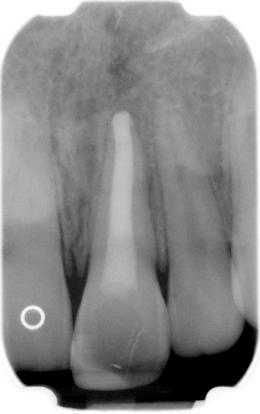

Deze worden ingesteld op een lengte zodanig dat niet voorbij de apex kan worden geboord. Vervolgens wordt met een licht schrapende beweging de kanaalwand aan alle kanten gereinigd. Bij alle methoden is de behandelmicroscoop onontbeerlijk om het resultaat te beoordelen. Nu wordt MTA (Pro Root) aangemaakt en het apicale deel van het kanaal (plus minus 5 mm) wordt hiermee gevuld. Een nat watje wordt op het aangebrachte MTA (Pro Root) geplaatst. Dit moet minstens 4 uur uitharden, daarom is een derde zittig nodig.

In de derde zitting wordt het watje verwijderd en de rest van het kanaal gevuld zoals gebruikelijk.